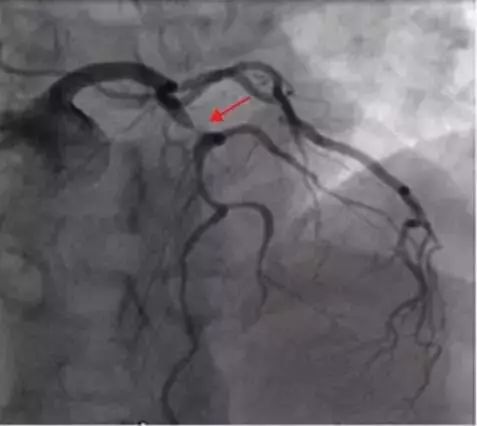

该患者心电图和De Winter研究中的心电图进行对比,不难发现其符合De Winter综合征的心电图表现,因考虑其前降支近端闭塞的可能,紧急行冠脉造影,提示前降支近端重度狭窄(图3),予PCI干预治疗,5天后患者顺利出院,胸痛未再发。

图3:冠脉造影提示前降支近端重度狭窄